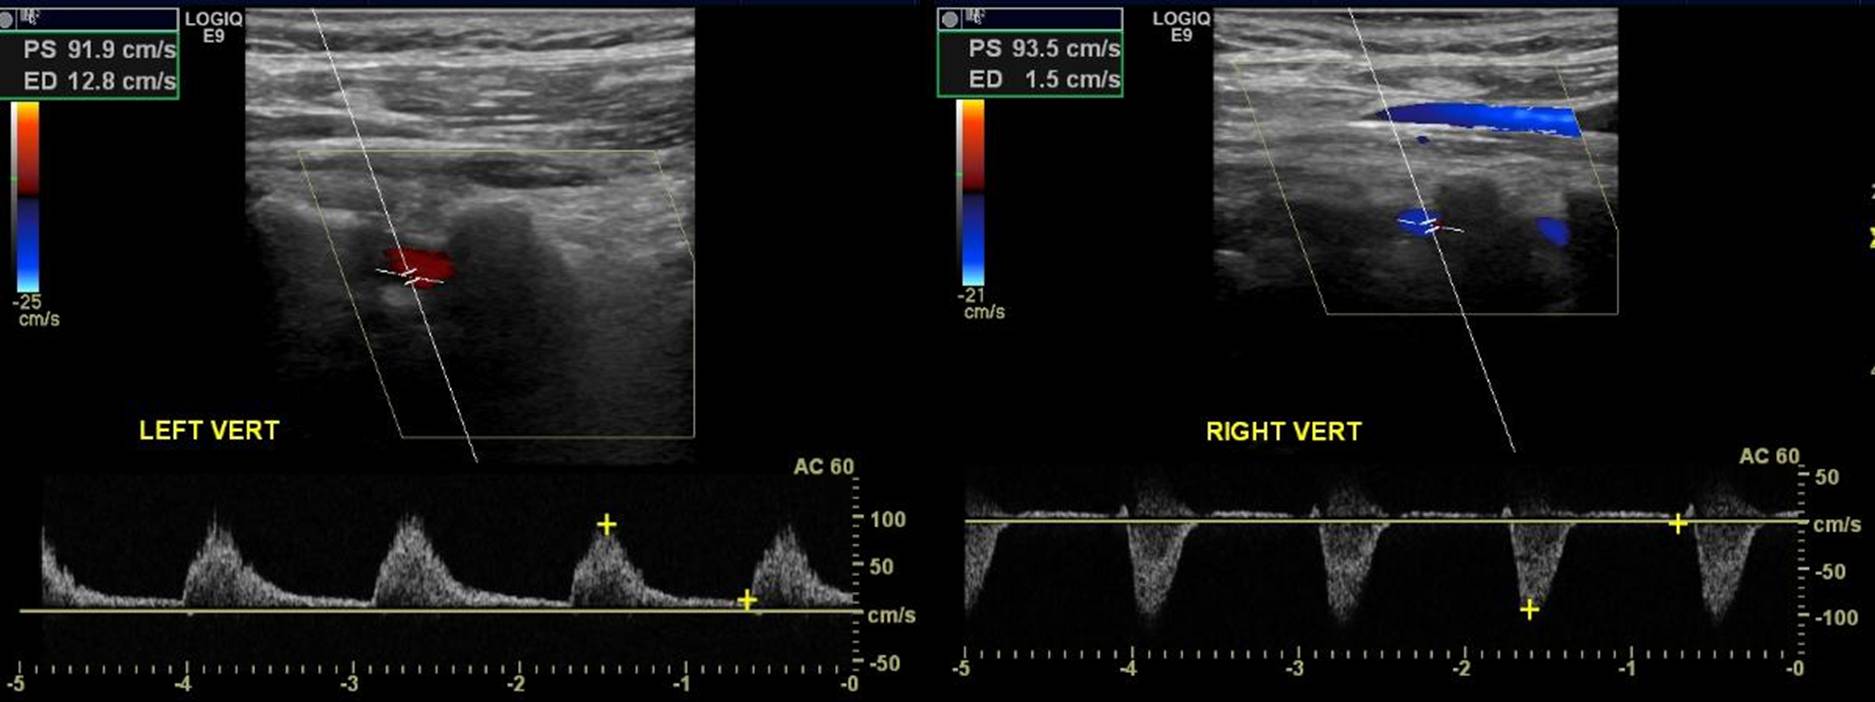

The worst outcome of subclavian artery stenosis is subclavian steal syndrome. In this condition, neurological symptoms occur because of the subclavian artery stenosis. Simply, when the arm needs more blood it “steals” it from the brain. The steal happens through the vertebral arteries. Blood will in these arteries will flow in the opposite direction. Instead of going to the brain, it will flow to the arm.

The next step is to use imaging. Imaging will make the diagnosis of the narrowing in the subclavian artery. Obviously, CT and MR are the best types of imaging for this. Then, imaging should identify the reverse flow in the vertebral artery. Duplex ultrasonography is the best type of imaging for identifying flow direction. Here is an example: